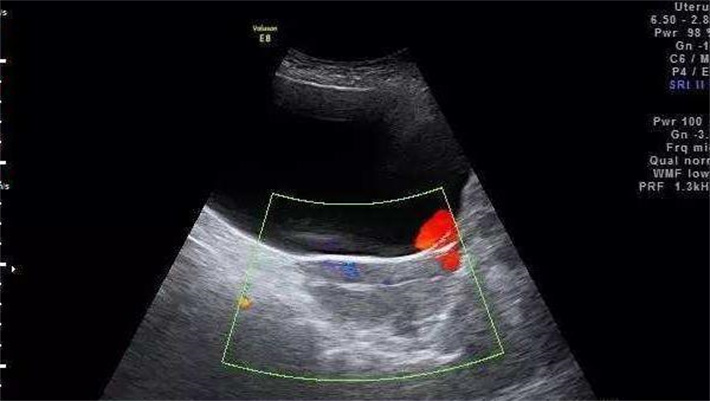

阴道超声检查也在黄体功能评估中发挥着重要作用。它能清晰观察卵巢中卵泡的发育、排卵情况以及黄体的形态、大小和血流信号等。通过超声检查,专家可以直接看到黄体的形成和发育过程,判断其是否正常。

除了血液检查,超声检查也是重要的监测手段。在胚胎移植后的特定时间,通过超声观察胚胎在子宫内的着床位置、发育形态以及胎心搏动等情况,进一步评估妊娠状态。若发现胚胎发育异常或有流产迹象,专家会综合分析各种因素,包括黄体功能、免疫因素等,制定个性化的保胎治疗方案,采取相应措施,如增加保胎药物的使用、给予免疫调节治疗等。